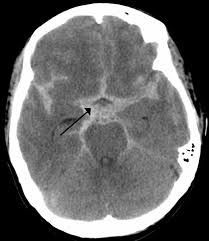

A subarachnoid hemorrhage means that there is bleeding in the space that surrounds the brain. Most often, it occurs when a weak area in a blood vessel (aneurysm) on the surface of the brain bursts and leaks. The blood then builds up around the brain and inside the skull increasing pressure on the brain.